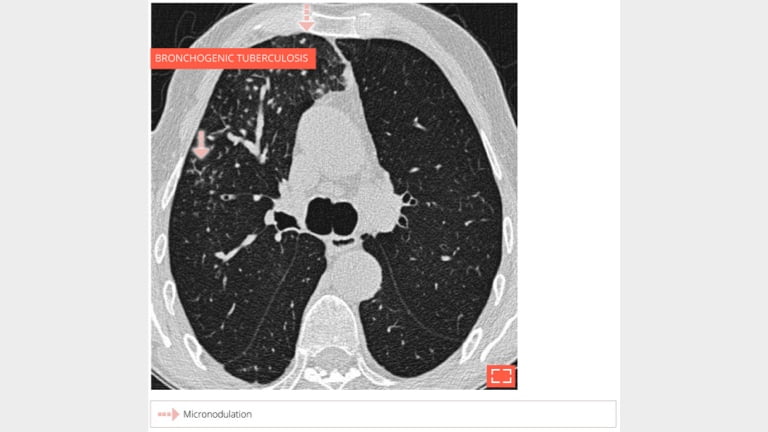

2. Micronodulation

micronodulation

Centrilobular and perilymphatic micronodulation.